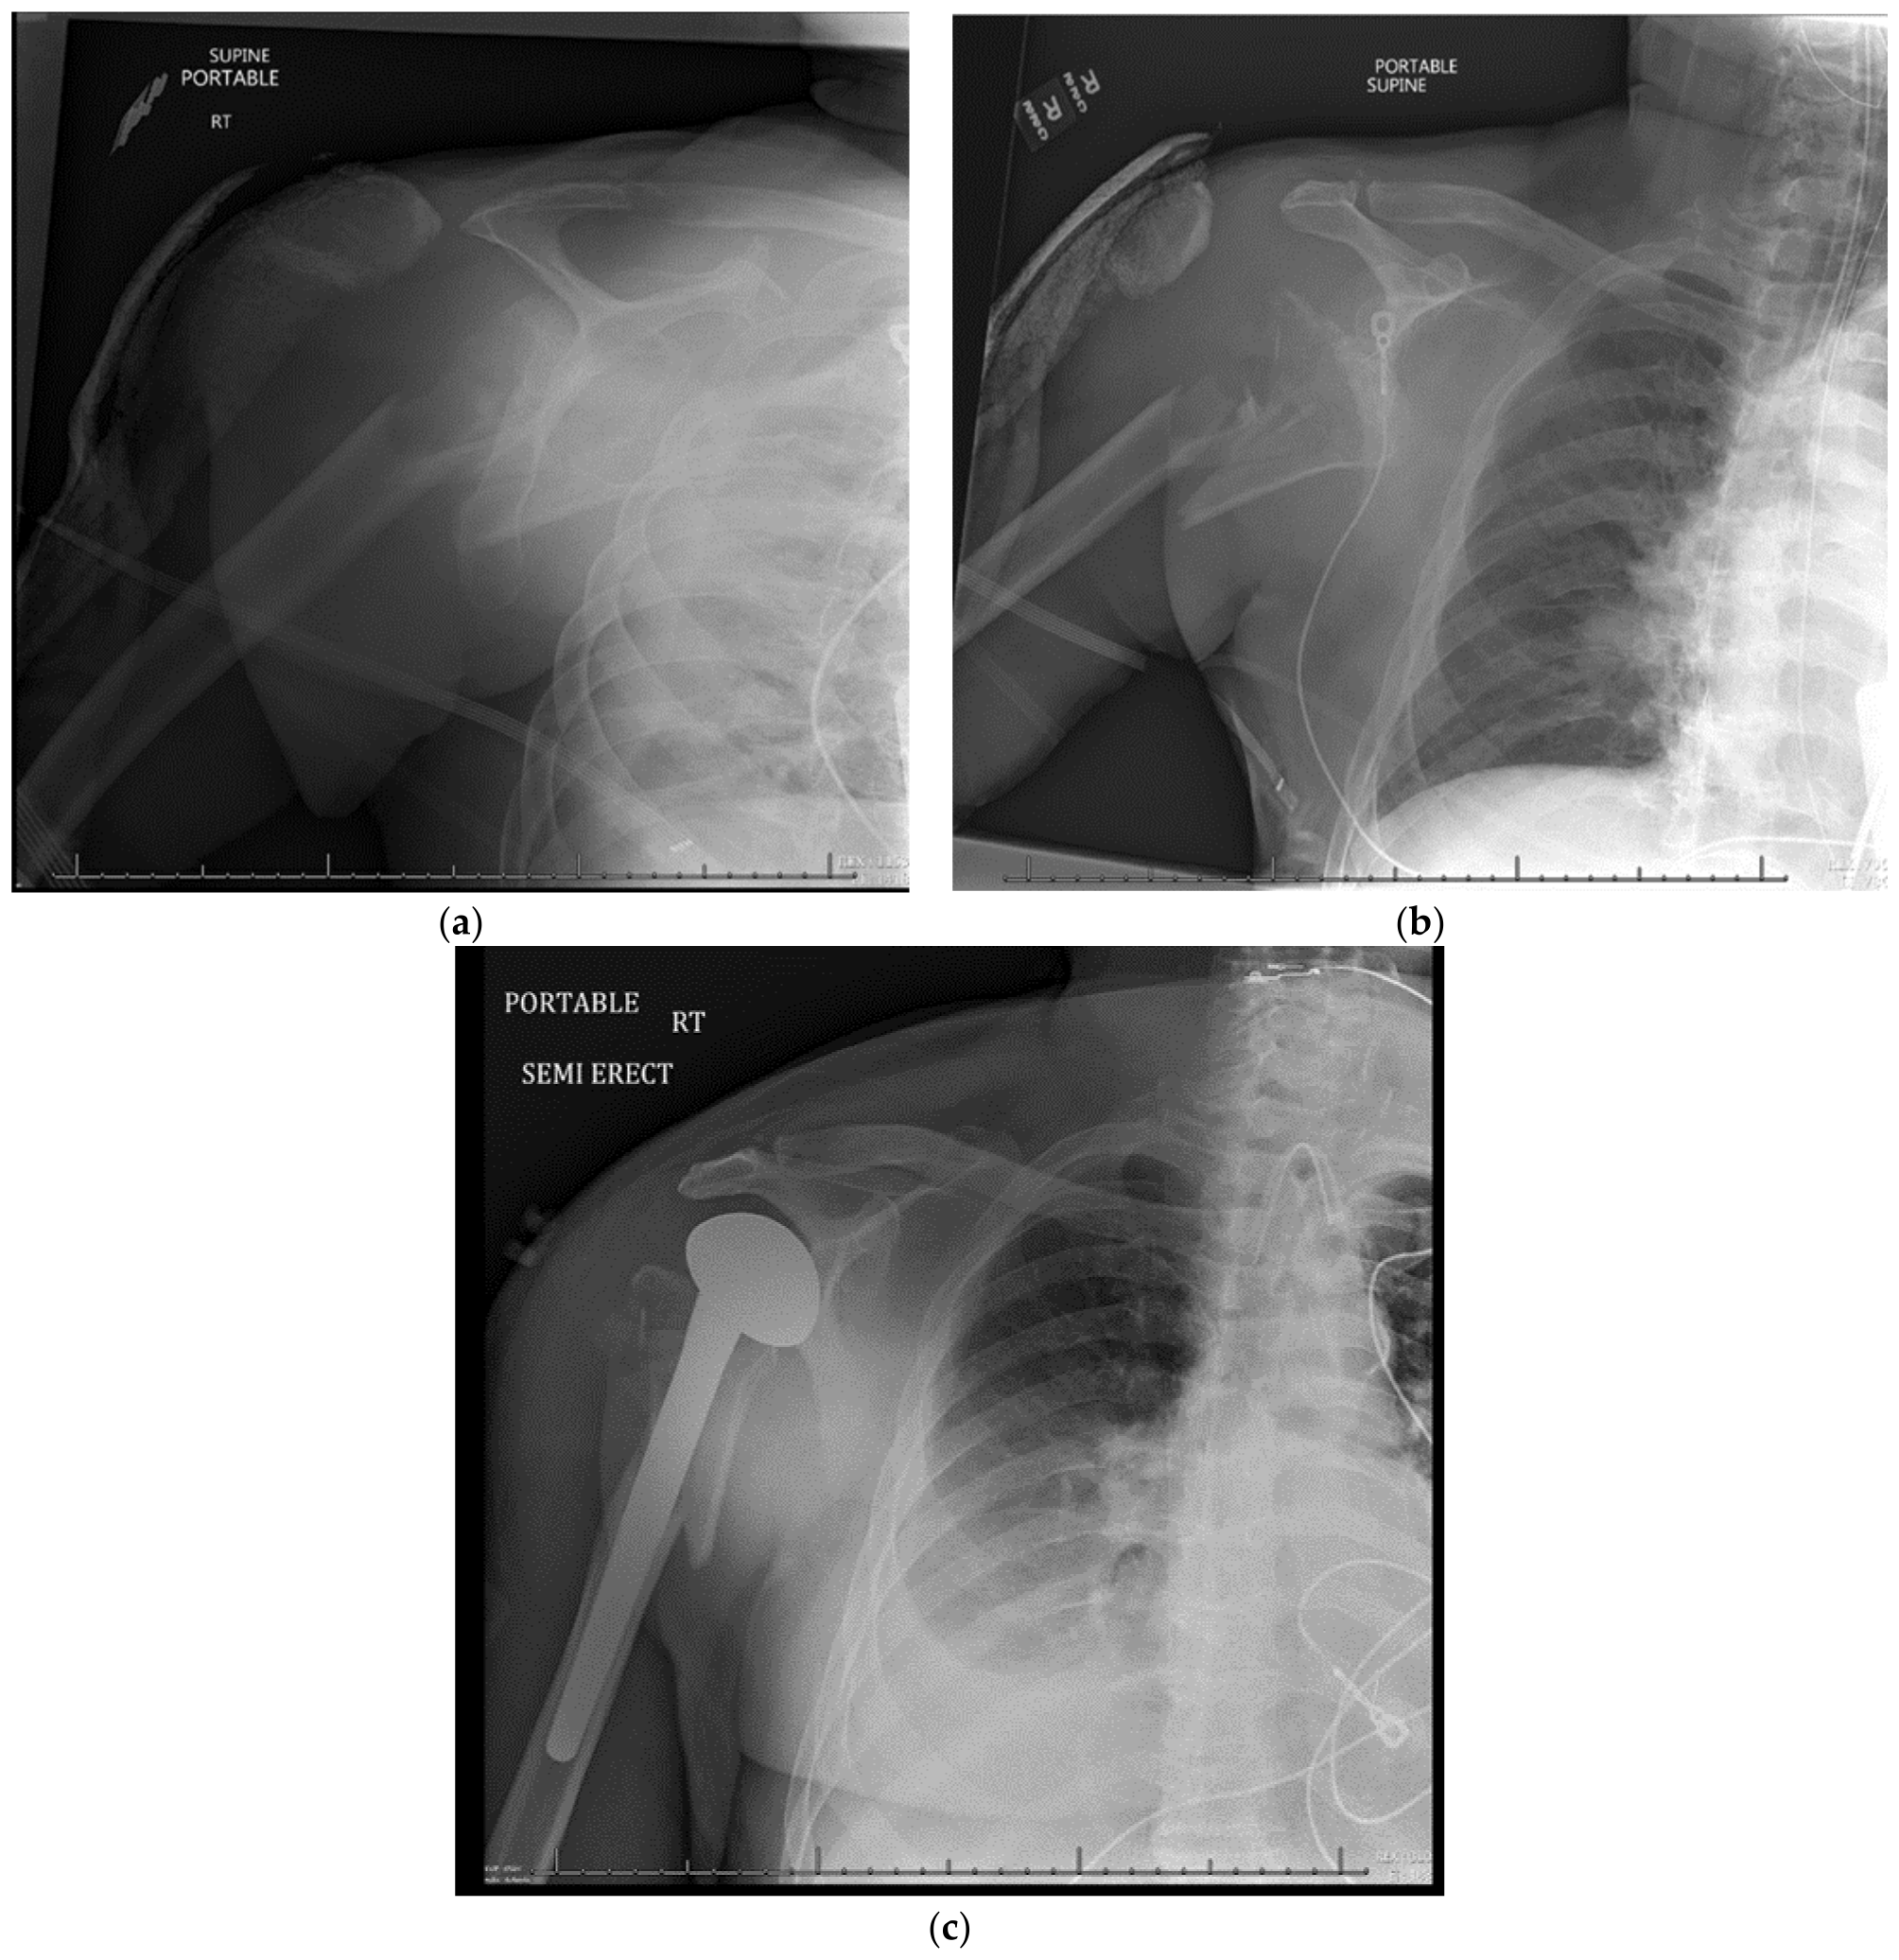

9. Open Reduction and Internal Fixation

10. Surgical Approach

10.2. Surgical Technique

10.3. Fracture Reduction

10.4. Fracture Fixation

11. Open Reduction Internal Fixation with an Intramedullary Nail

12. Surgical Approach for ORIF with an Intramedullary Nail

12.2. Surgical Technique

12.3. Fracture Reduction